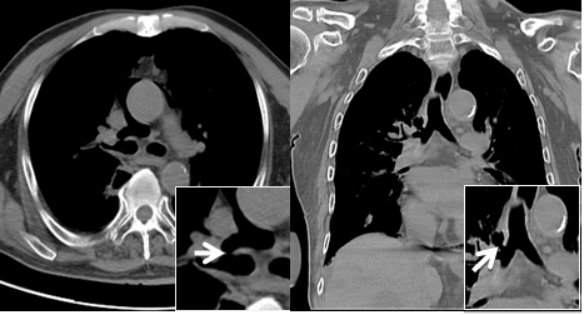

1 资料与方法患者男性,70岁,因“胸闷3 d,加重伴呼吸困难1 d”于2019年9月13日入外院。患者3 d前无明显诱因出现胸闷,伴全身乏力,夜间睡眠差(可平卧),初未予重视,1 d前胸闷加重,伴呼吸困难、运动耐量明显下降、大汗淋漓、皮肤湿冷,至外院就诊,查心电图(图 1):交界性逸搏,肢体导联低电压,Ⅰ、Ⅱ、Ⅲ、aVF、V4、V5、V6导联ST段抬高0.15 mV~0.4 mV,aVR、aVL、V1导联ST段压低0.05 mV~0.2 mV,aVL、V1导联T波倒置;心肌酶:CKMB 27.1 U/L,NT-proBNP 3 298 pg/mL。外院考虑不排除急性心肌梗死导致的心源性休克,经口气管插管接呼吸机辅助通气后为进一步诊治转入本院。患者家属否认患者有外科手术、外伤、气胸及哮喘发作史,起病以来无畏寒、高热,大、小便正常,既往1年余前因“反复咳嗽伴咳血丝痰”在外院诊断为右肺门鳞癌,合并高血压病、2型糖尿病,经依托泊苷+顺铂化疗,具体剂量不详。2019-09-07复查胸部CT提示右肺病灶较前缩小。体格检查:体温35ºC,血压86/43 mmHg,心率53次/min,呼吸15次/min(经口气管插管呼吸机辅助呼吸),神志昏迷,双侧颈静脉怒张,气管居中,桶状胸,胸廓对称,双肺呼吸动度对称,叩诊呈清音,听诊呼吸音清,双肺未闻及干湿性啰音,心前区无隆起,叩诊心界消失,心音低弱遥远,桡动脉、股动脉搏动可触及。入院后复查心电图(图 2):心房颤动,肢体导联及胸导联低电压,各导联ST-T改变较前相似,未见明显动态演变。血常规:白细胞1.27×109/L,中性粒细胞1.15×109/L,血红蛋白98 g/L,降钙素原43.01 ng/mL,超敏肌钙蛋白Ⅰ 0.048 ng/mL。急诊冠脉造影(图 3):左前降支近段轻度狭窄,中段心肌桥,收缩期重度狭窄,左回旋支远段中度狭窄,右冠中段重度狭窄,TIMI血流均为3级。患者超敏肌钙蛋白I未见明显升高,冠脉血流通畅,排除急性心肌梗死引起的ST段抬高。心脏彩超:气体干扰较大,仅能从剑突下观察,心包腔内未见积液。胸片(图 4):纵隔内可见条状透亮带,心影周围可见一弧形透亮带,考虑心包积气、纵隔气肿。入院诊断为“①心包积气、②纵隔气肿、③右肺鳞癌”,经剑突下途径行心包穿刺置管术+闭式引流术,术后液封瓶内见气体逸出,患者血压较前逐渐上升。完善胸部CT(图 5):右侧肺门增大,右主支气管与上叶支气管壁交界处见小缺损,考虑支气管破裂,心包、纵隔、胸腔及腹腔积气。纤维支气管镜(图 6)检查:可见右主支气管距隆突约1 cm处见破损,破损处周围组织呈白色,不排除癌组织浸润可能。病因考虑为右肺门鳞癌浸润右主支气管,穿孔后经纵隔与心包腔形成瘘道,引起心包积气。经过上述治疗后患者血流动力学稳定。

| 图 5 胸部CT(纵隔窗)白色箭头所指处为右主支气管与上叶支气管壁交界处见小缺损,考虑为右支气管破裂 |